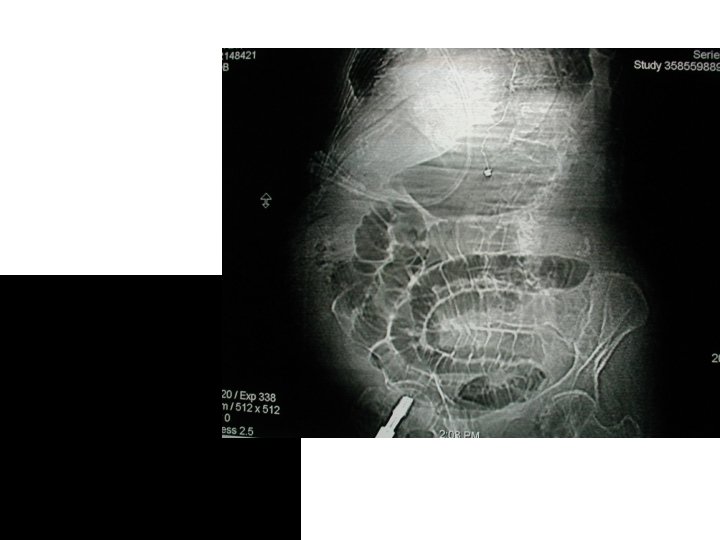

RADIOLOGICAL DIAGNOSIS Obstructed small bowel is characterized by straight segments that are central and lie transversely. No gas is seen in colon Jejunum regularly spaced valvulae conniventes giving a concertina / ladder effect. Ileum featureless

At first gas shadows appear followed by fluid levels. Number of fluid levels is directly proportional to the degree of obstruction & to its site. Impacted foreign bodies and gas in gall stone ileus may also be visible in radiographs.

GAS FILLED LOOPS MULTIPLE FLUID LEVELS